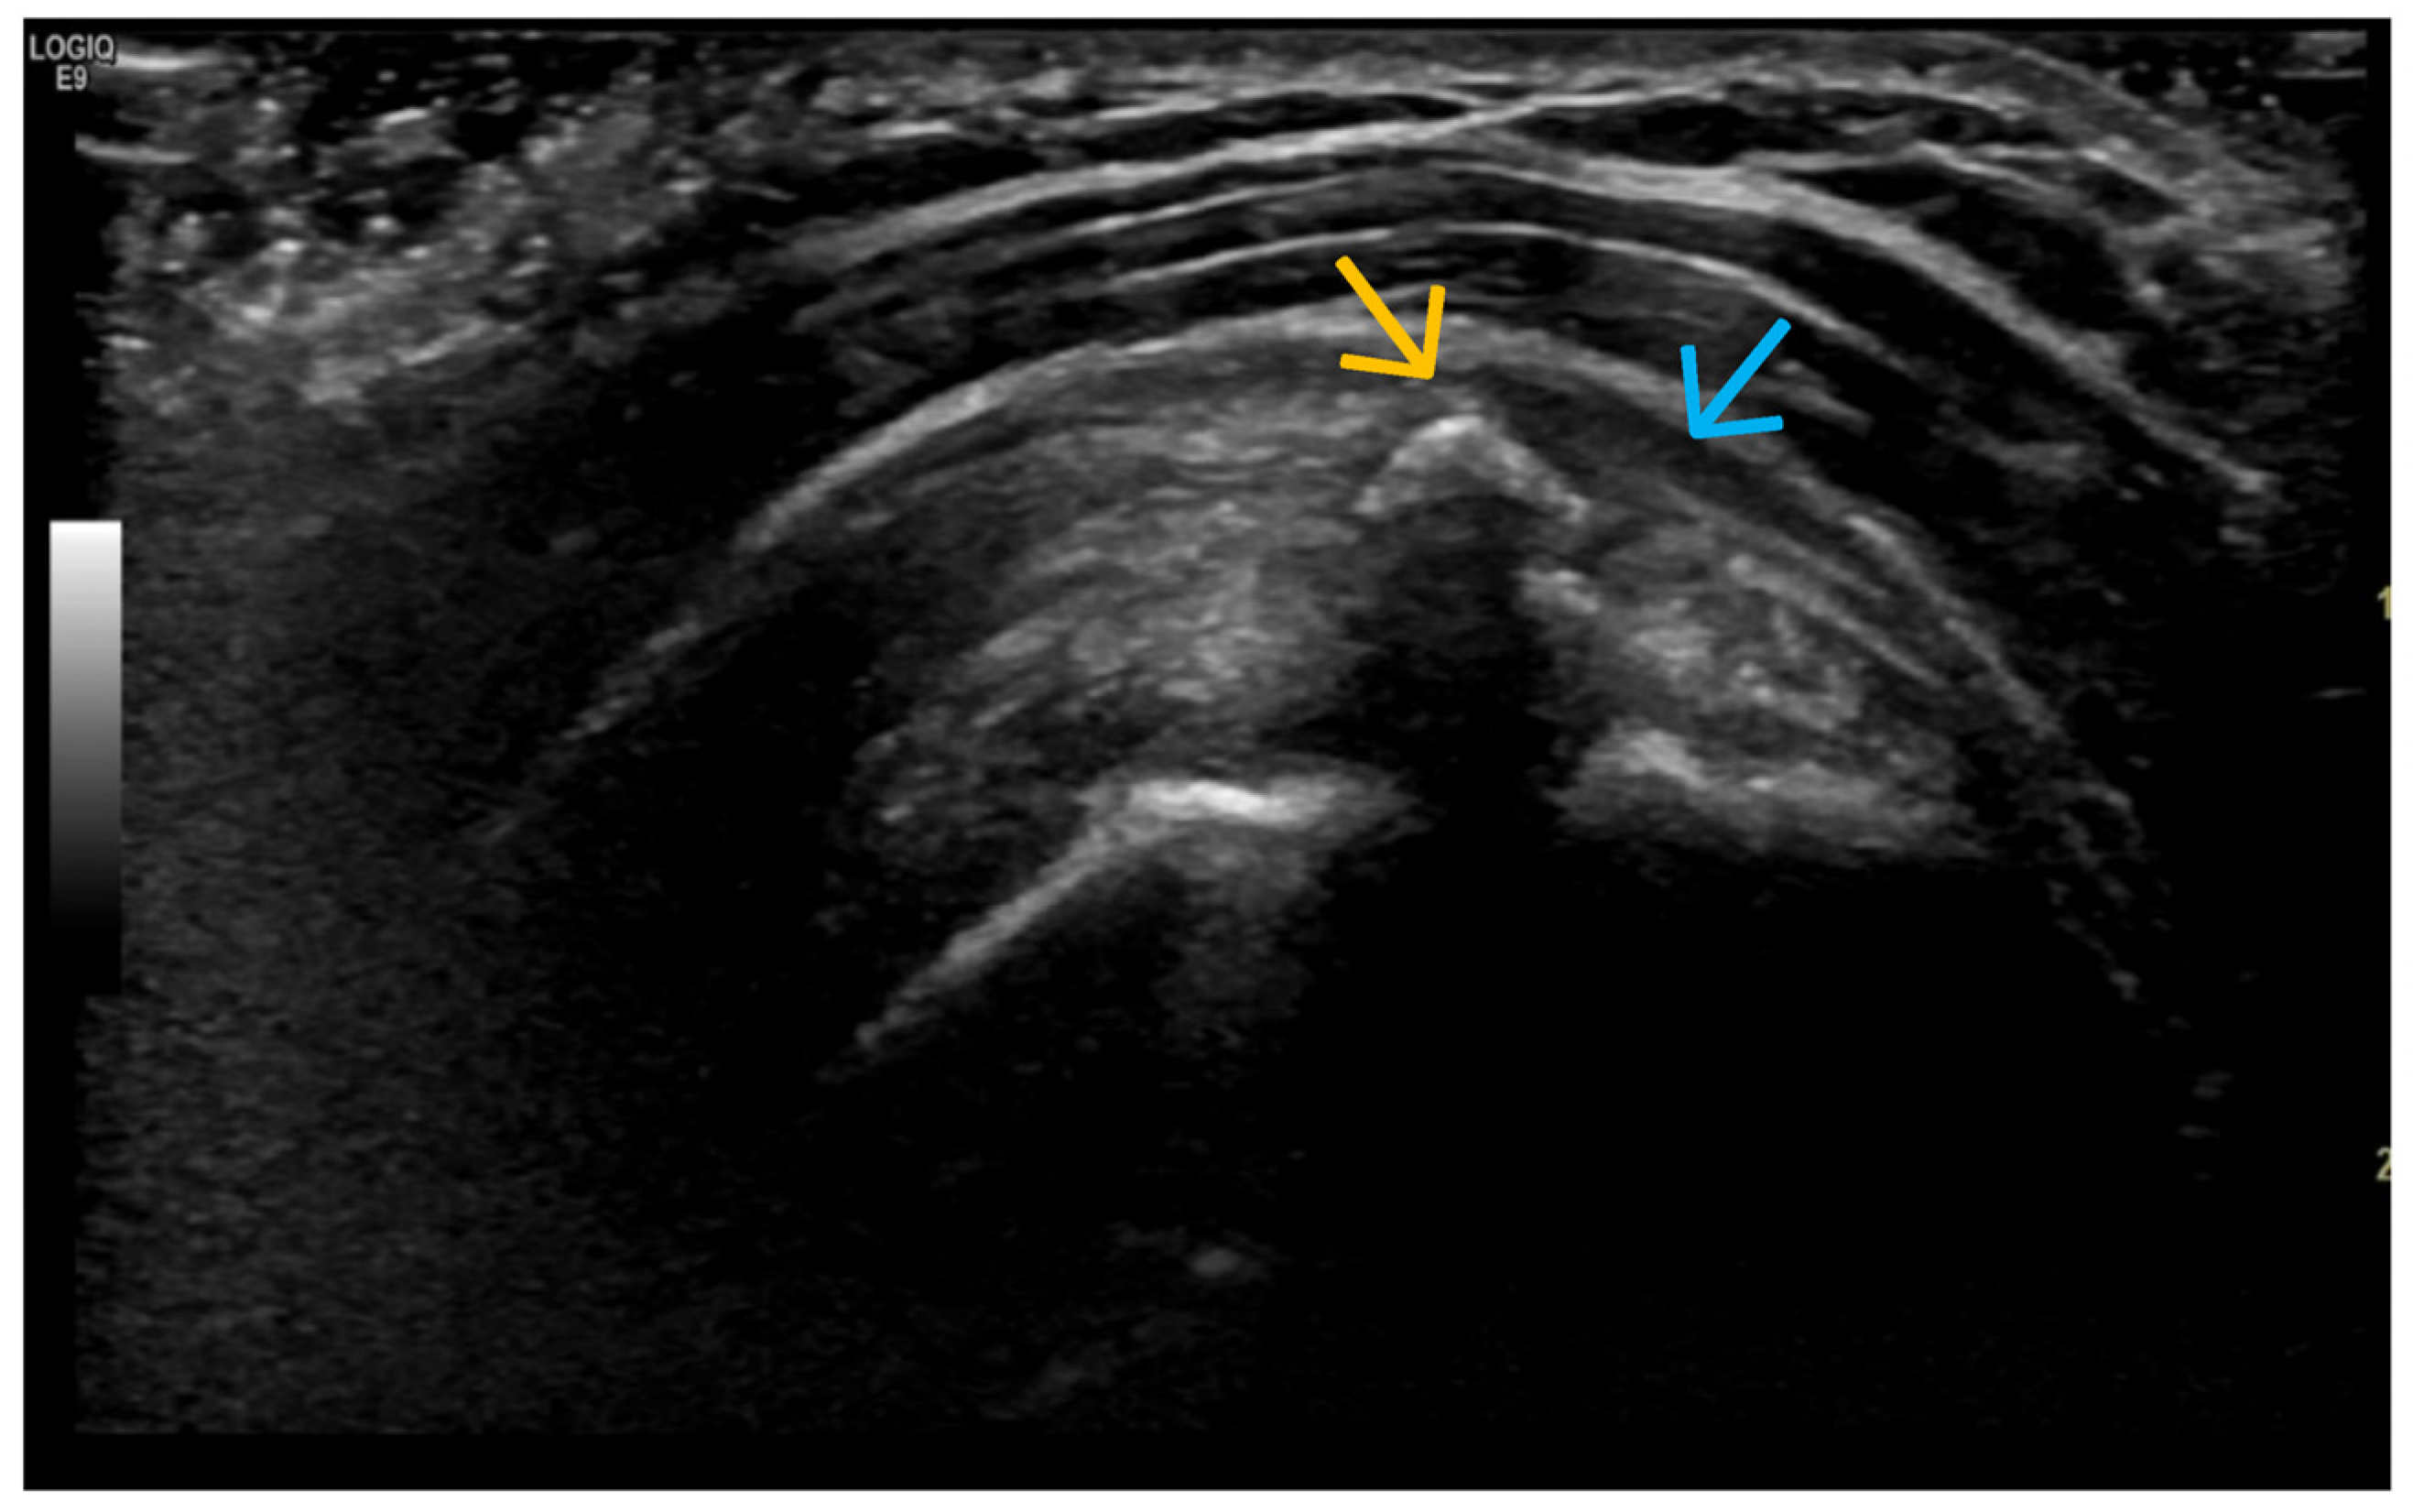

3. Suggestions for US Phenotypes

- Predominant synovial proliferation, fat pads, and Hoffa synovitis (with a small amount of intra-articular effusion);

- Altered subchondral bone (superficial bone erosions or osteophytes);

4. Examples of US Phenotypes